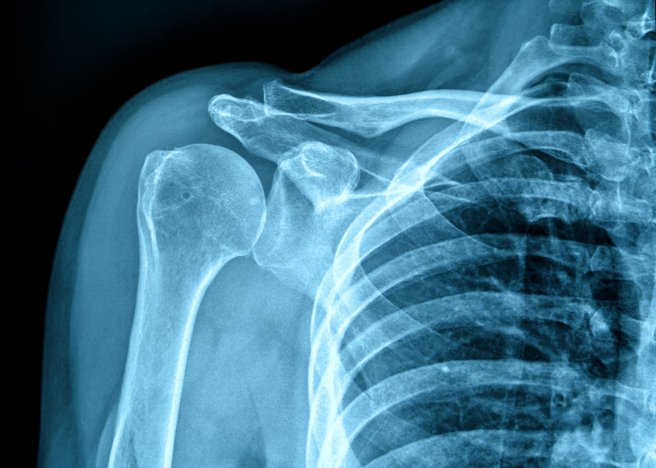

医师发现她骨纤维发育不良,而且颈部的副甲状腺有颗肿瘤,不仅如此,她全身骨质疏松,骨头的骨密度都不正常,认为主因就是副甲状腺肿瘤,医师赶紧替她进行肿瘤切除手术,术后秀秀体内的血钙明显下降,补充钙和维生素D后,她的骨质也逐渐升高,数值接近正常人,之后医师还帮秀秀矫正O型腿,让她恢復正常生活。

臺北荣民总医院资料显示,副甲状腺(parathyroid gland)是4个像豆般大的腺体,副甲状腺荷尔蒙的功能是帮助身体维持钙和磷质的平衡,也是调节血钙的重要荷尔蒙之一,可促使骨骼释放出钙,增加小肠对钙的吸收及调节尿钙的排泄,若副甲状腺荷尔蒙过多,会导致大量钙离子由骨骼进入血液,造成骨骼中的钙质流失,因而出现骨质疏松的状况。